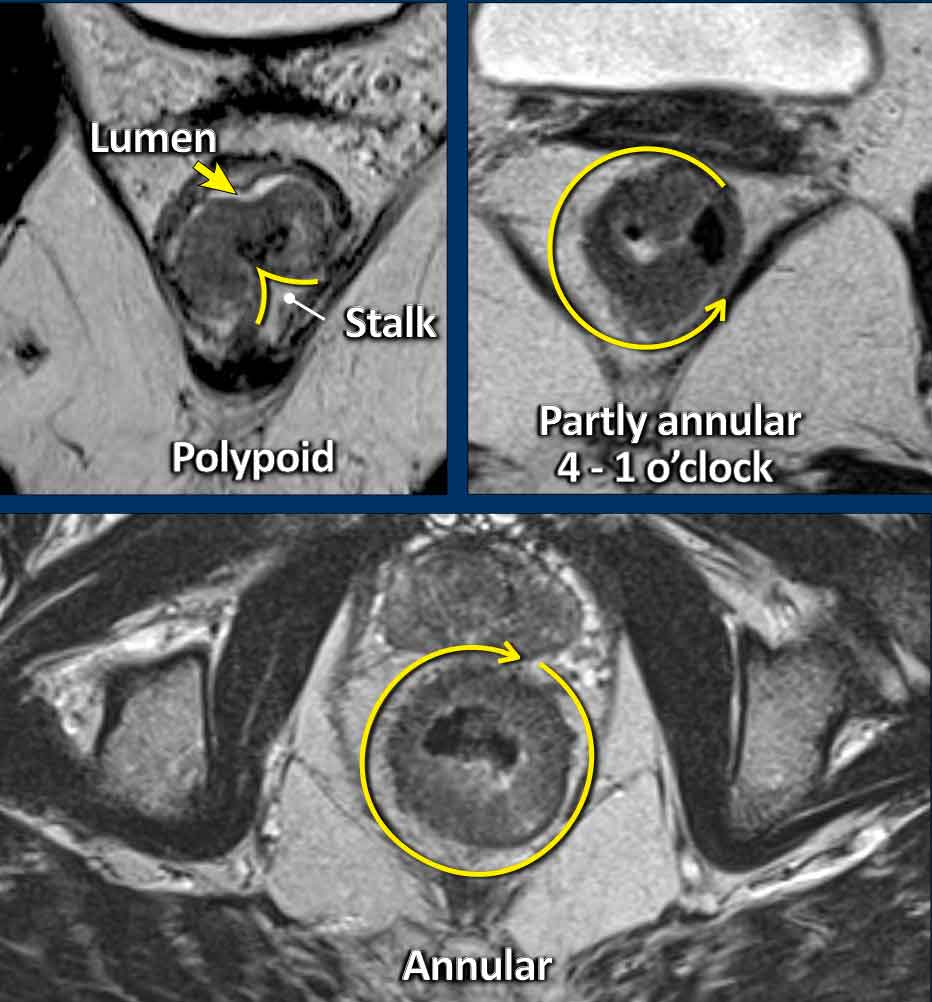

T3 Tumors

T3 tumors extend beyond the muscularis propria into the mesorectal fat.

MRI findings:

• Interruption of the hypointense muscularis propria

• Spicular or nodular tumor signal extension into the mesorectal fat

Image

This partly annular tumor (8–12 o’clock) invades the perirectal fat, with an anterior MRF margin <1 mm (arrow), consistent with cT3ab MRF+.

• Intact muscularis propria is visible from 12 to 8 o’clock

• Right-sided interruption of the muscularis, with nodular tumor extension into the perirectal fat (arrowheads)